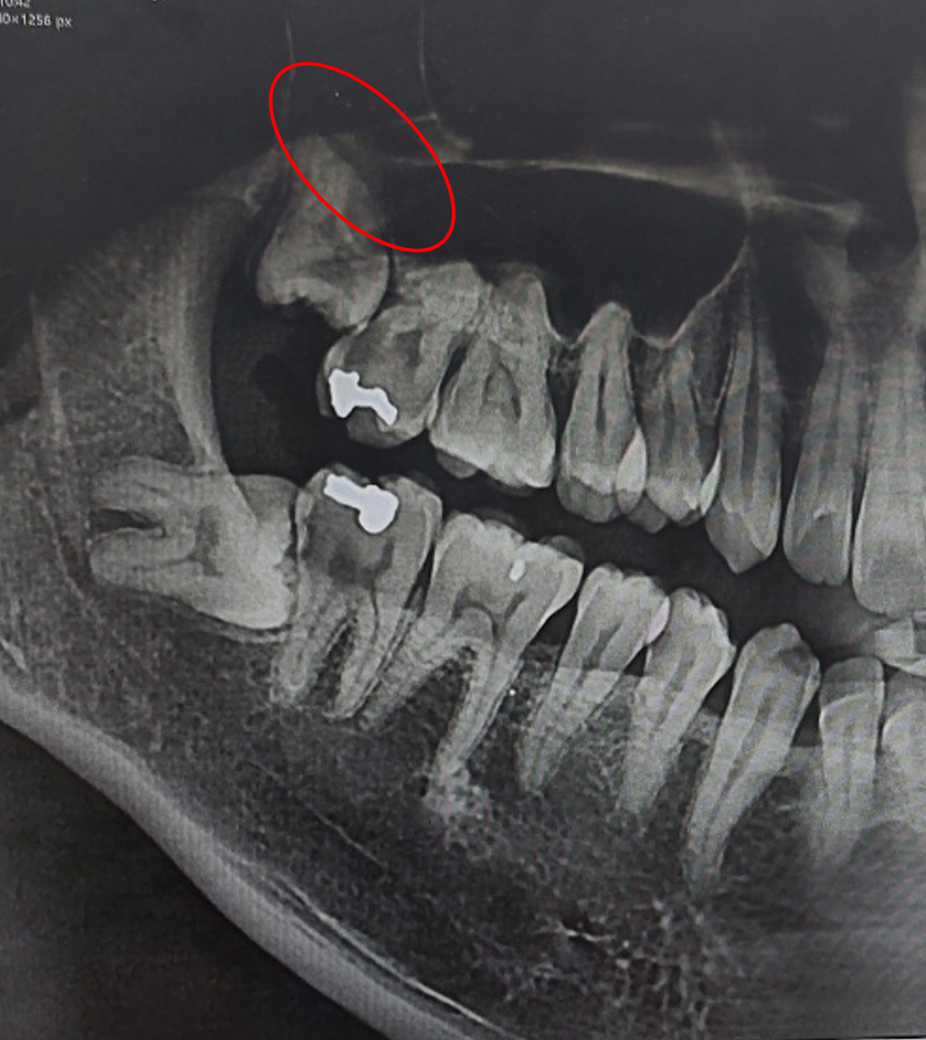

오늘 사랑니 발치를 위해 치과에서 CT 찍고 날짜 잡고 왔는데요.

CT 보기 전에도 말해주셨지만 사랑니 발치할 때 위쪽 막? 부분(사진 표시된 부분)이 제가 너무 얇아서 찢어져서 천공이 생길 수 있다고 하더라구요.

그래서 따로 전화와서 대학병원 추천을 해주는데 이게 진짜 대학병원 가서 뽑아야될 정도인가요?

일단 저 사랑니 옆에 이가 충치가 많이 생겨 신경치료 받고 있고 (3차 치료 받았고 끝나서 다음 방문 때 씌울거라네요)사랑니 자체도 드러난 부위는 충치가 꽤 생긴 상태로, 다음 방문 때 상담받긴 할건데 이거 그냥 근처에 사랑니 발치 잘하는 다른 치과 가도 되지 않을까하여 여쭤봅니다.

해당 매복 정도와 상악동과의 거리를 판단했을 때는 대학병원에서 발치해야할 정도로 난이도가 높습니다. 또한 앞쪽 치아에 비해 매복된 정도가 커서 시야 확보도 상당히 어려울 것으로 보이며 발치 시 많은 시간이 필요할 것으로 보입니다.

1. 위쪽 사랑니의 경우 상악동이라는 구조물과 근접하고 발치 중 상악동막이 천공될 가능성도 있습니다.

2. 아래쪽 사랑니의 경우 비교적 신경관과 가깝습니다.

• 현재 사진상으로 난이도가 높은 사랑니 발치입니다. 대학병원이 아니더라도 사랑니 발치 경험이 풍부한 구강외과 전문의에게 발치를 받는 것이 안전합니다.